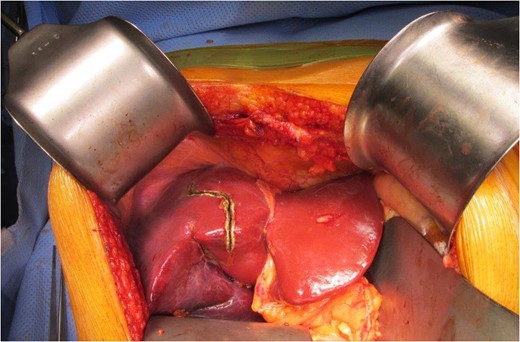

Neoadjuvant therapy was completed 1 month before surgical intervention. The patient underwent bilateral ureteral stents placement and an exploratory laparotomy in the lithotomy position. Intraoperative ultrasonography localized the tumor without showing any unexpected lesions. A right extended hepatectomy proceeded in the standard manner (Figs 3 and 4).

The colon was fully mobilized, and the mesentery was transected with high ligation of the ileocolic and middle colic pedicles. Because of the patient’s inferior mesenteric artery stump bulky disease, the surgeons performed a complete para-aortic lymphadenectomy and en bloc resection. The abdominoperineal resection was performed without incident. A pelvic drain was placed. His 15-day hospitalization was complicated by anemia requiring transfusions, lower-extremity deep vein thrombosis and prolonged ileus.